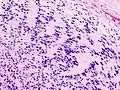

Micrograph of a schwannoma showing both a cellular Antoni A area (top) and a loose paucicellular Antoni B area (bottom). HE stain. | |

Verocay bodies are seen histologically in schwannomas.

Antoni A area of schwannoma with Verocay bodies (one annotated by circle)